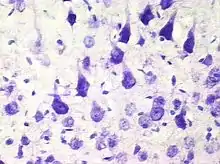

Пирамидальные нейроны, или пирамидные нейроны — основные возбудительные нейроны мозга млекопитающих. Также обнаруживаются у рыб, птиц, рептилий. Напоминают по форме пирамиду, из которой вверх ведёт большой апикальный дендрит; имеют один аксон, идущий вниз, и множество базальных дендритов. Впервые были исследованы Рамон-и-Кахалем. Отмечены в таких структурах, как кора мозга, гиппокамп, миндалевидное тело (амигдала), но отсутствуют в обонятельной луковице, стриатуме, среднем мозге, ромбовидном мозге, спинном мозге. В кортикальных структурах млекопитающих представляют наиболее многочисленную популяцию возбудительных нейронов.